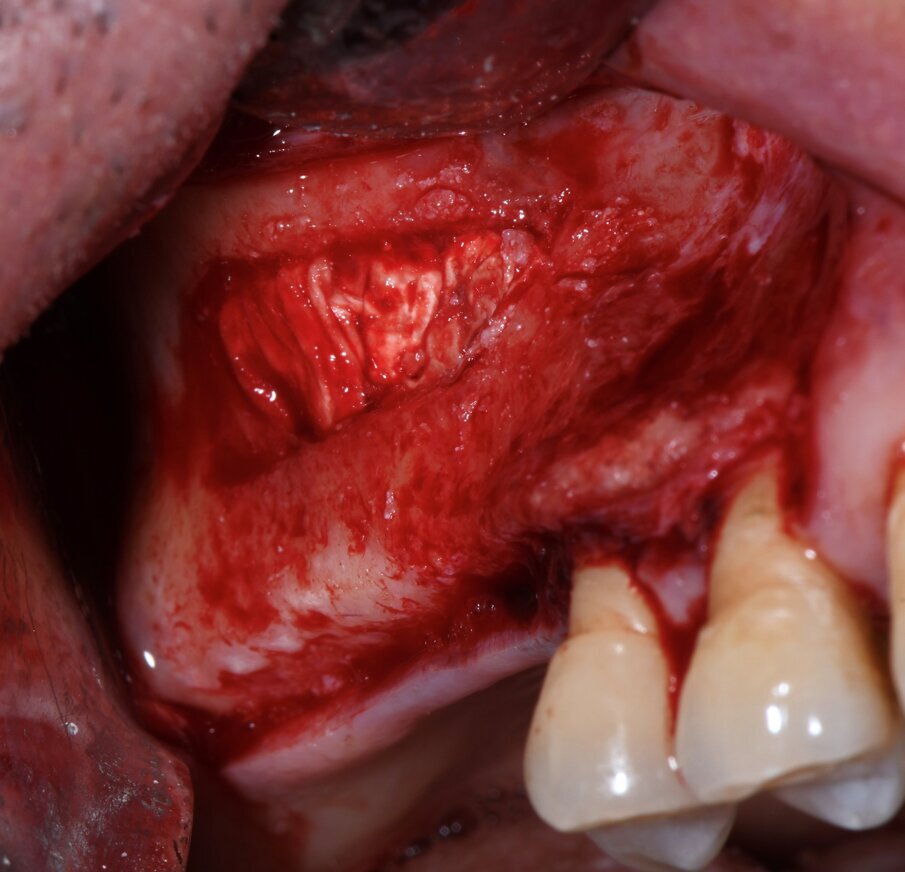

Quattro pazienti con severa atrofia verticale dell’osso alveolare della regione posteriore del mascellare superiore, che necessitavano di una riabilitazione implantoprotesica unilaterale della zona edentula, sono stati trattati con la tecnica del Sinus Pack. Dopo 6 mesi è stata eseguita una TC per valutare il volume osseo ottenuto, sono stati inseriti gli impianti ed è stata inoltre prelevata una carota ossea di 4 mm con una fresa carotatrice ossea. Sono stati sottoposti a trattamento tre uomini e una donna (range di età tra 36 e 74 anni); non sono state registrate complicanze intra o postoperatorie. Confrontando le misurazioni eseguite sulla TC preoperatoria e dopo 6 mesi dall’intervento, è stato riscontrato un guadagno verticale di osso pari a 6,95 mm (Figg. 1-4). Nella valutazione dell’analisi istologica e istomorfometrica della carota ossea prelevata si è riscontrato un completo riassorbimento della membrana, una neoformazione ossea e solo una piccola percentuale di innesto ancora presente (Figg. 5-7).